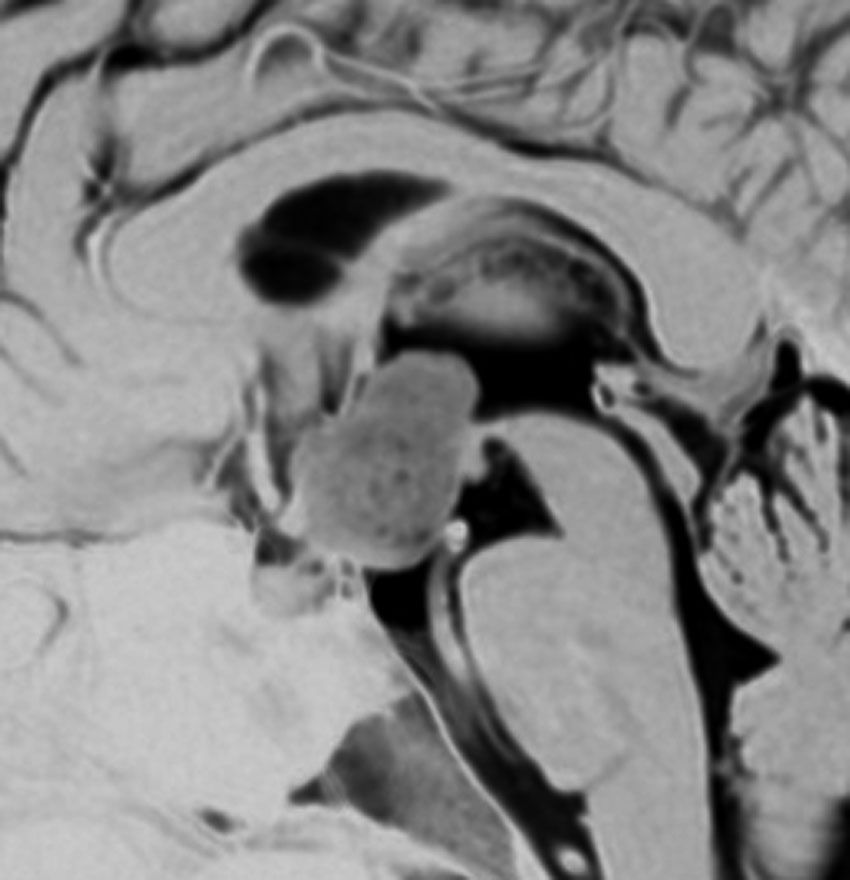

2歳の時に歩行障害で転倒しやすくなって発症しました。巨大な小脳虫部の毛様細胞性星細胞腫です。後頭下開頭で亜全摘出して,翌年,残っていた小さな残存腫瘍を全摘出しました。

cerebellarpilo3cerebellarpilo4

16歳になってとても元気に学校へ通っています。こんな小脳でもちゃんと歩けるようになります。残っているわずかな小脳機能を手術で守ることはとても難しいと言えます。